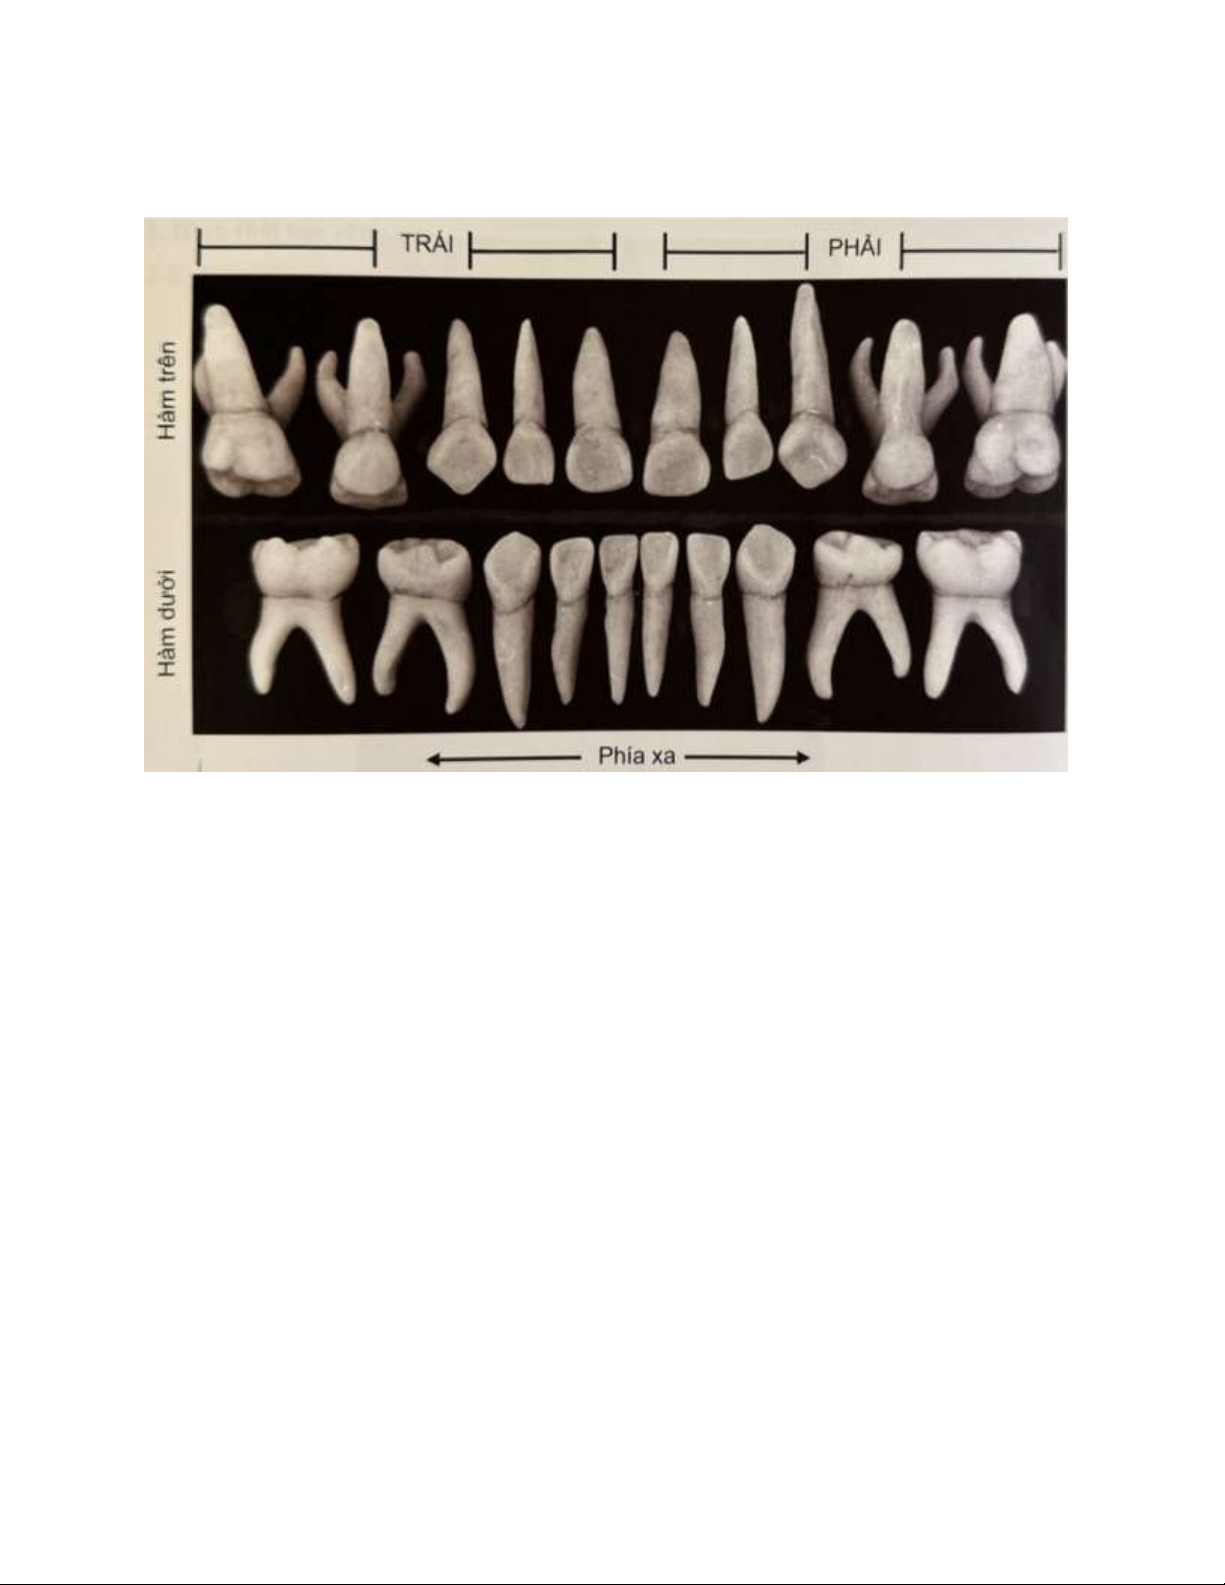

dưới, đánh số từ trái sang phải từ trên xuống dưới . lOMoAR cPSD| 59561451 Hình 5.1 . Răng sữa

Hình 1. Bộ răng sữa nhìn từ phía gần. Giống như ở răng vĩnh viễn, bờ cắn răng

cửa trên nằm trùng với trục răng hoặc lệch ngoài và bờ cắn răng cửa dưới nằm

ngay hay lệch trong trục răng. Ở răng cối, mặt nhai có thể thấy từ mặt xa hơn từ

mặt gần. Cuối cùng, chú ý phần ba chóp răng trước cong ra ngoài, nhất là ở các răng trên.